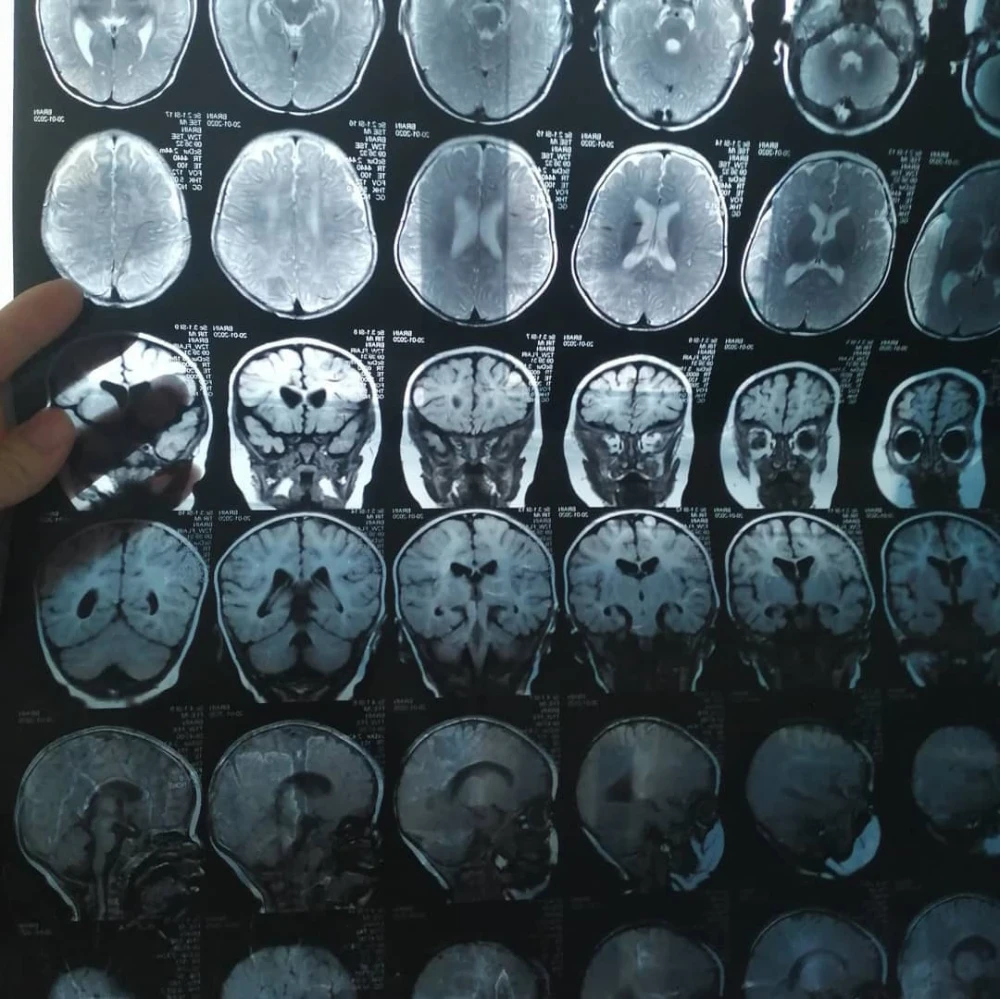

Бегимайдын кызынын диагноздору көп, ага жардам керек.